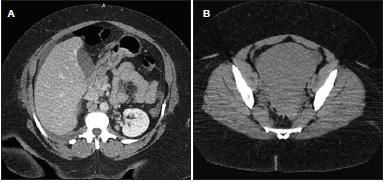

The presence of significant perihepatic ascites on the lower cuts of the chest CT scan (Figure 2A) suggested a concomitant abdominal pathological condition. A CT scan of the abdomen revealed a large pelvic mass (10 × 12 cm) anterior to the uterus, with non-visualization of the right ovary (Figure 2B).

Figure 2 – Perihepatic ascites on the chest CT scan suggested an abdominal pathology (A). A CT scan of the abdomen revealed a large pelvic mass anterior to the uterus (B).